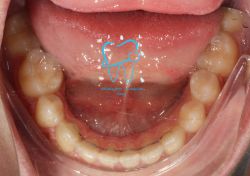

1982 visualizzazioni Una paziente di 12 anni si presenta alla nostra osservazione con una malocclusione in arcata superiore ed inferiore. La situazione appare complicata, oltre che da un affollamento notevole in arcata superiore, dalla agenesia dell'elemento 4.5 e con il 3.6 molto distrutto e difficilmente recuperabile per il futuro in maniera pervedibile. Si decide a questo punto per un trattamento ortodontico fisso con il movimento mesiale degli elementi posteriori e la chiusura degli spazi solo con denti sani e pienamente funzionanti ed evitare successivamente costosi procedimenti protesici.